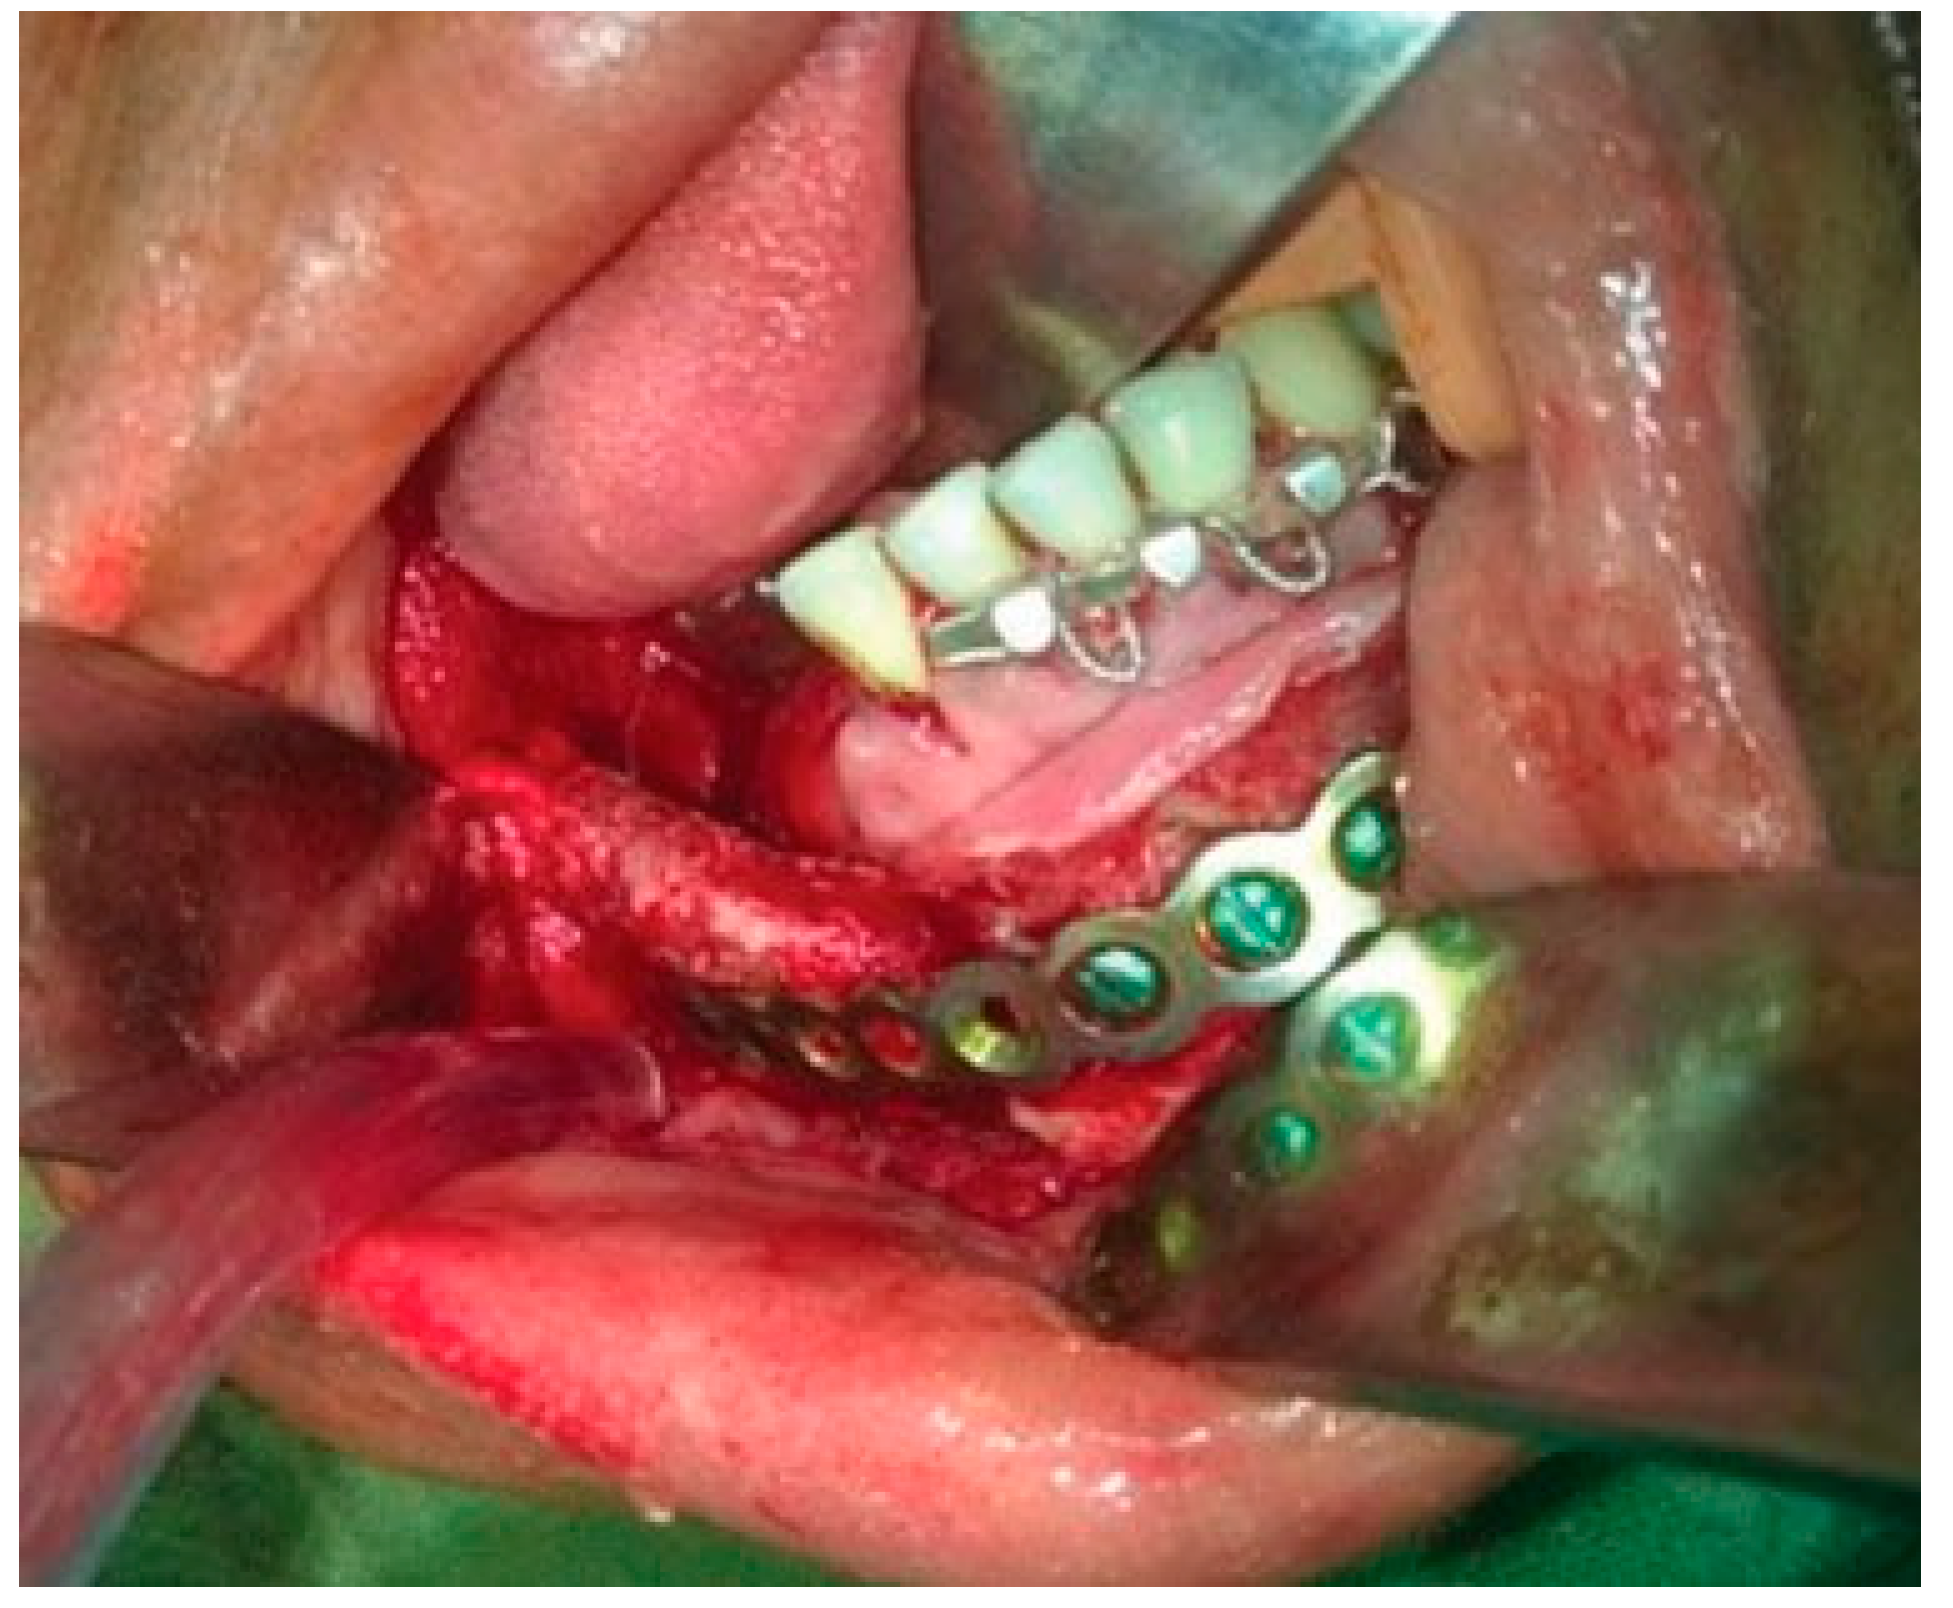

A reconstruction plate was then contoured along the resected mandible and fixed to the anterior region of the mandible with the help of five bicortical screws. A 5 cm × 2 cm cortico-cancellous bone graft was then harvested from the iliac crest to reconstruct the resected body of the mandible (Figure 8). A double-layer closure of the wound was done to obtain watertight closure.

Figure 8. Reconstruction with condylar reconstruction plate and corticocancellous bone graft.